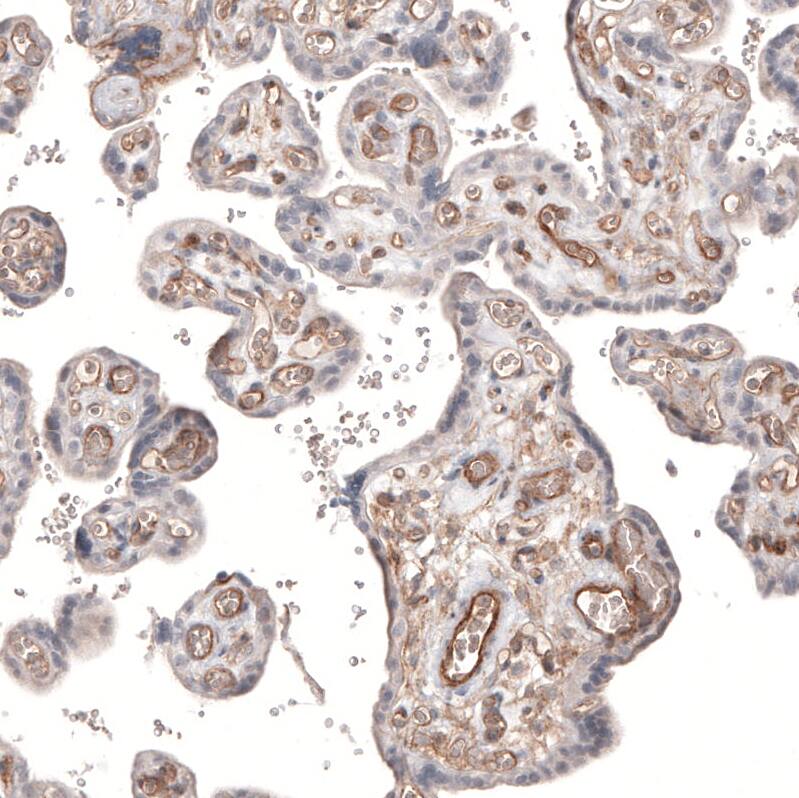

Staining of human placenta shows moderate membranous positivity in endothelial cells.